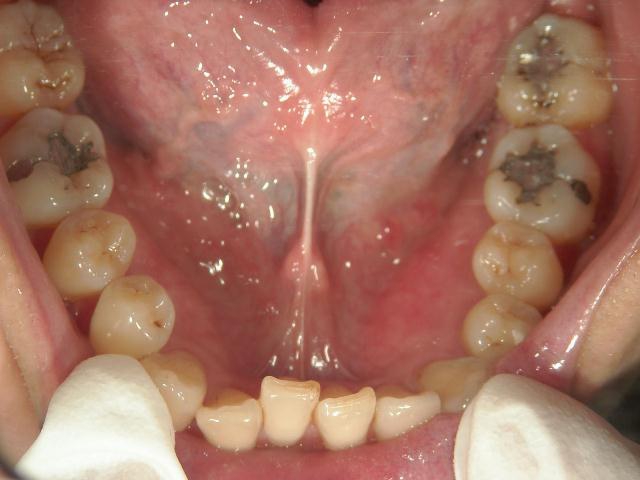

矯正歯科 治療前 下顎